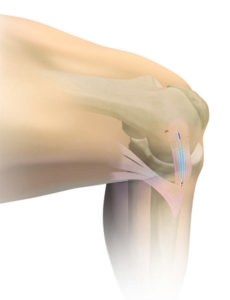

Operative Therapie: MPFL-Rekonstruktion

Bei ca 80% der ersten Kniescheibenluxationen kommt es zu einem Riss eines wichtigen Bandes, welches die Kniescheibe strecknah als einziger Stabilisator auf der Innenseite stabilisiert. Das sogenannte MPFL (Mediales patellofemorales Ligament) ist eine trapezförmige Struktur. Die Operation wird von uns mit einer minimalinvasiven Technik durchgeführt, bei der wir die Stabilität mit einer körpereigenen Sehne wiederherstellen. Die Sehne wird vom hinteren Oberschenkel entnommen und mit zwei kleinen Ankern an der Innenseite der Kniescheibe befestigt. Anschliessend wird unter Röntgenkontrolle der exakte Punkt am Oberschenkel festgelegt, an welchem das neue Band in jedem Winkelgrad die identische Spannung hat. Gerade diesem Operationsschritt wird oft zu wenig Bedeutung zugemessen, was wiederum zu einem erhöhten Anpressdruck der Kniescheibe und dauerhaften Schmerzen oder zu einer weiterhin bestehenden Instabilität führt. Die Befestigung hier erfolgt mit einer Schraube die der Körper in Knochen umbaut.